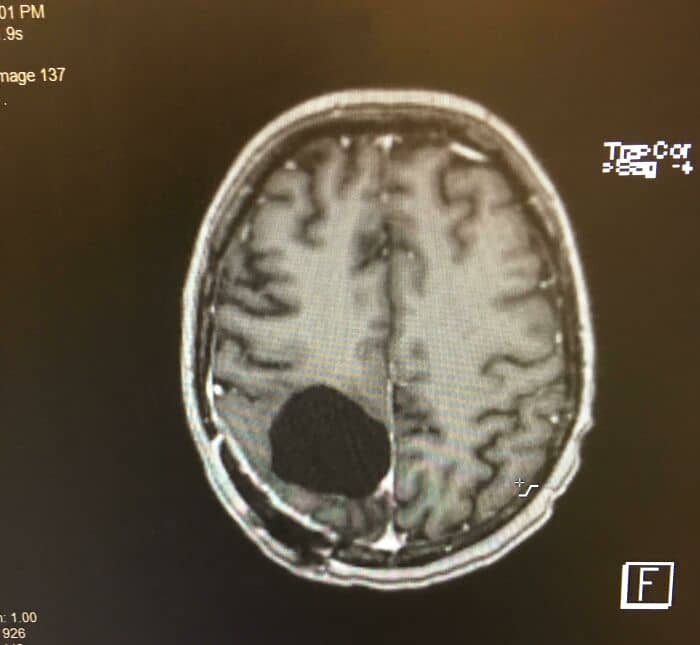

#80 Dandy-Walker Syndrome

It is a condition that develops due to congenital failure of cerebellar vermis development that leads to blockage of CSF circulation. Clinical features include bulging fontanelle, irritability, vomiting ,poor feeding and lethargy.